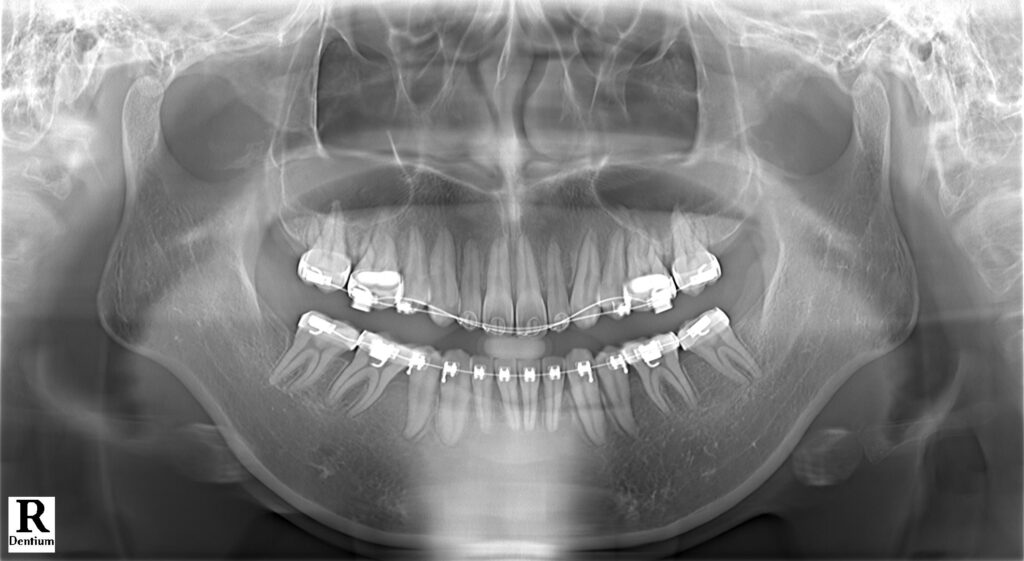

Điều trị những trường hợp bật chân răng do niềng hỏng là rất khó khăn và phức tạp. Trường hợp này là một bệnh nhân được niềng răng ở nước ngoài, sau đó hết thời gian lao động mà bệnh nhân chưa hoàn thành điều trị và được chuyển về việt nam để điều trị tiếp. Tuy nhiên, khi BN đến với phòng khám làm gặp tình trạng mất torque rất nặng ở hàm dưới đến mức trên CBCT không còn cả bản xương ngoài- trong. Nên nhóm răng cửa hàm dưới không thể can thiệp gì hơn.

Kế hoạch: chỉnh torque, đóng nốt khoảng và chỉnh khớp cắn 2 hàm, hoàn thiện và kết thúc trong 1 năm